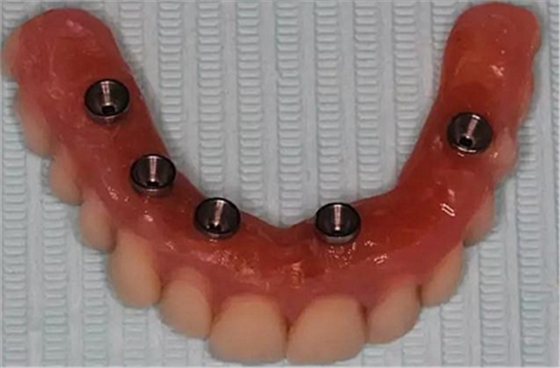

牙列缺失患者由于支持、固位、穩(wěn)定不足導(dǎo)致義齒效果差,如果在牙槽嵴內(nèi)植入種植體,種植體可以根據(jù)種植體數(shù)量不同提供義齒不同程度的固位、穩(wěn)定、支持,獲得不同的修復(fù)效果。當(dāng)單頜牙列缺失患者使用1-2顆植體,植體和覆蓋義齒之間可以靠一些附著體如磁性附著體、桿卡式附著體、球帽式附著體等裝置連接,主要提供固位和穩(wěn)定作用,少量的支持作用,當(dāng)單頜牙列缺失使用4顆植體時(shí),很大部分支持力可以由植體承擔(dān),當(dāng)使用4顆以上植體時(shí)可完全由種植體提供義齒的支持、固位和穩(wěn)定,甚至制作為不可摘戴的全口固定種植義齒。